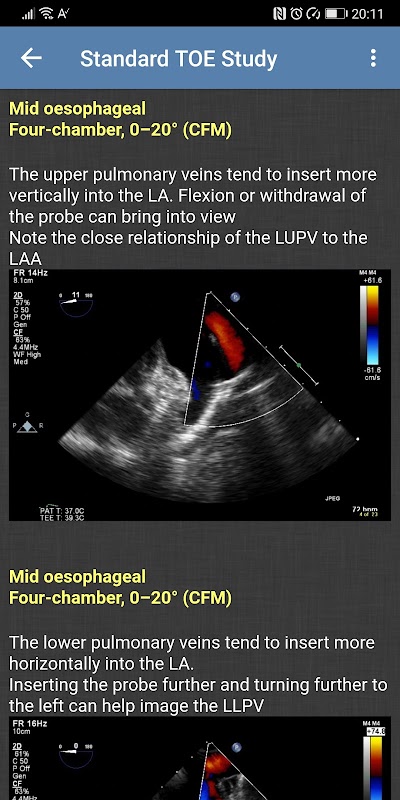

- Étude TOE standard